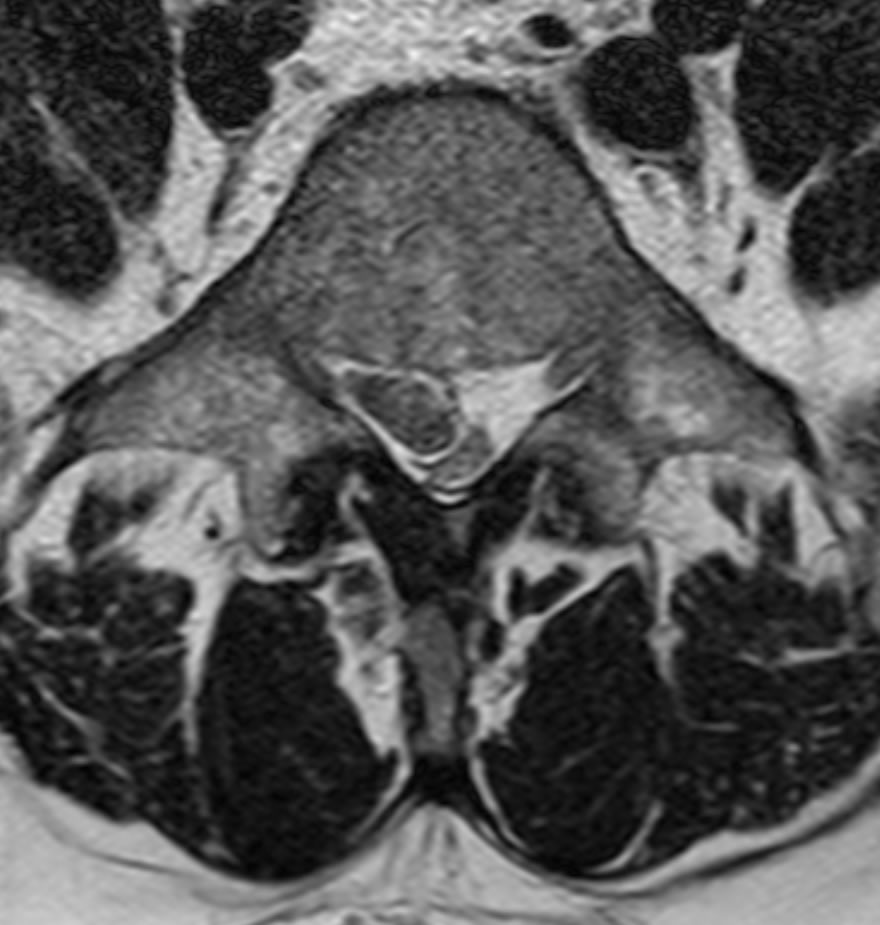

La hernie discale est une lésion provenant d'une dégénérescence d'une partie d'un disque intervertébral. En général, il y a une ouverture de l'anneau fibreux qui laisse sortir une partie du noyau pulpeux (mou) du disque intervertébral. Le fragment de disque mou s'échappe dans le canal rachidien et vient comprimer un nerf spinal. La compression et irritation du nerf provoque les douleurs de type "sciatique".

L'investigation principale est l'IRM de la colonne soit lombaire pour les hernies discales lombaire ou cervicale pour les hernies cervicales. Parfois il est utile de faire un éléctroneuromyogramme (ENMG) qui permet d'évaluer le degré d'atteinte de la conduction nerveuse.